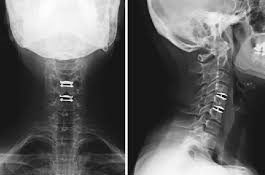

The cervical spine functions to support the skull protect the spinal cord and allow a diverse range of head movement. Systemic complications include blindness blood clots in the legs neurological pulmonary cardiac complications even death. Pain usually comes and goes with flare-ups followed by symptom-free periods. Cervical disk replacement surgery involves removing a diseased cervical disk and replacing it with an artificial disk. Before this procedure was available the affected disk was removed and the vertebrae above and below were fused together to prevent motion. Compression of the cervical nerve root may occur due herniation of disk material or bony osteophytes that impinge on the cervical nerve root.

Many people have reported experiencing at least some pain relief from injections for a cervical herniated disc. Degeneration of disk levels above or below surgery level. The patients usually recover well after the surgery. An artificial disc such as the Prestige LP TM cervical disc made by Medtronic is placed between two adjacent cervical vertebrae to replace a diseased cervical disc. Causes Symptoms Diagnosis Treatment A New Non-Drug Treatment For Cervical Dystonia Neck And Shoulder Pain While. Treatment is more effective the earlier it is started but depends on the cause of the coma as this defines which type of diabetic coma a patient hasThe three causes of diabetic coma are severe hypolgycemia or lowering of the blood sugar level diabetic ketoacidosis.

Anterior Cervical Diskectomy and Fusion and Artificial Disk Replacement Risks. Active or recent infection neuropathic joint complete paralysis of deltoid or rotator cuff muscles debilitating medical status. 1 a soft pulpy nucleus pulposus on the inside of the disc and 2 a surrounding firm structure known as the annulus fibrosus. He also whips up a great spinach salad with raisins pine nuts and cinnamonSee more ideas about Lower blood sugar Diabetic diet Diabetic tips. Generally the cervical vertebrae are approached from the anterior surface and after discectomy an anterior fusion is performed. Cervical artificial disc replacement is a type of joint replacement procedure.